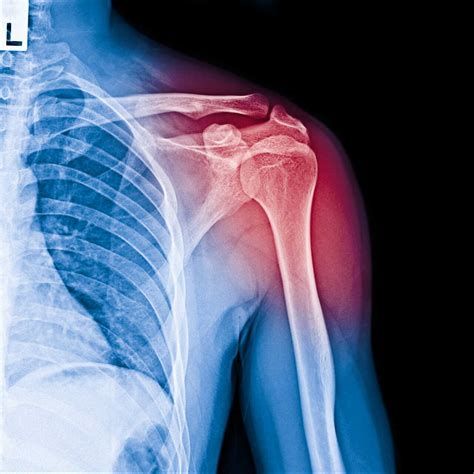

뼈 골절 수술비용은 골절 부위, 골절의 복잡성, 병원 규모, 사용 재료, 입원 기간 등에 따라 크게 달라질 수 있습니다. 아래는 최신 자료와 실제 경험담을 토대로 주요 부위별 평균 비용과 예상 범위를 정리한 내용입니다.

골절 부위별 수술비용에 큰 영향을 미치는 주요 요소는 아래와 같습니다.

- 골절 부위의 해부학적 특성

- 부위가 클수록(예: 대퇴부, 척추 등) 수술 난이도와 위험도가 높고, 사용되는 재료도 더 복잡하거나 많아져 비용이 증가합니다.

- 예를 들어, 머리뼈/얼굴뼈 골절 진료는 발생 빈도가 높지만, 실제 진료비 비중은 넓적다리뼈(대퇴부) 골절이 가장 높으며, 이는 해당 부위 수술이 복잡하고 후유증·합병증 가능성이 커 고가 치료가 요구되기 때문입니다.